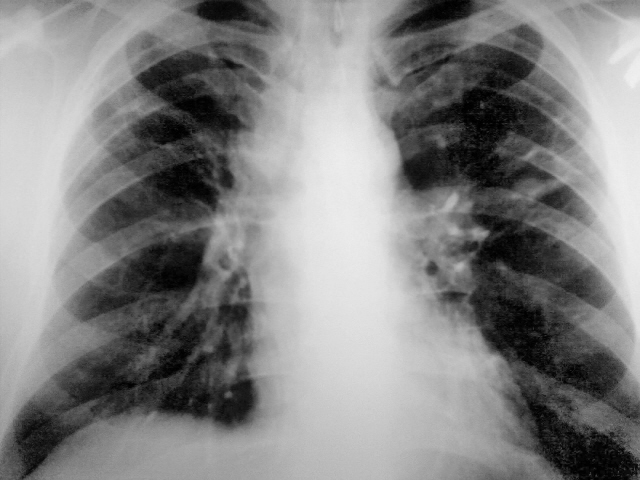

Потупил с диагнозом инфильтр tbs с поражением в/гр и периферич л/у. Болеет около месяца. Не контактен, пов t до 38. Менингиальные знаки 3+. Умер через 30 часов, на вскрытии...

Заподозрить еще как можно. Доказать, проблемно. Но подняв литературу узнал что картина типична для хронического... на фоне которого развивается... Обратите внимание на кисты слева, а справа формируется аналогичная.

Кавернозный туберкулез, ослабление иммуннитета. Присоединение неспецифической инфекции привело к сепсису и меннингиту, смерть, скорее, от менингита. Смущает эмфизема легких, но на легочную дистрофию не тянет. Конечно, досужие вымыслы. На КТ данных за медиастинит нет, кистовидные полости с толстыми стенками. СПИД всё бы объяснил.

Совершенно верно! Имеет место хронический лейкоз на фоне которого пневмония с распадом, кисты справа следствие таких же пневмоний. Остается вопрос почему кровь не набрали с самого начала.

Возраст около 45, точно не помню. На снимках еще стоял. Пока все мимо. Напомню увеличены в/гр и периферические л/у.

Неет причина смерти совсем иная. Уточню тут две патологии, одна обуславливает другую.

Раз увеличены все л/у, может, лейкоз.